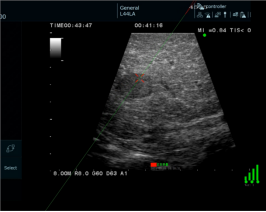

近日,云南省第一人民医院肝胆胰外科主任晋云带领团队成功实施了“磁导航技术引导下的腹腔镜肝脏肿瘤微波消融手术”。较目前常见术中导航系统而言,这一技术能更精准选择肿瘤穿刺位置,规划穿刺路径及评估路径安全,减少反复无效穿刺带来的肝损伤,更有效引导腹腔镜肝脏消融手术,确保了消融的成功率和安全性。

此次接受手术的患者患有肝脏肿瘤,传统消融方式如同“盲打”,需凭借医生经验反复穿刺调整,才能将消融针精确送达目标位置,不仅手术时间长、创伤大,也增加了并发症风险。而团队此次采用的 “磁导航腹腔镜微波消融”新技术,则完美解决了这一临床痛点。

晋云表示,该技术犹如为手术医生安装了“精准的GPS实时导航系统”。手术中,通过磁导航系统,虚拟的穿刺路径清晰明了,并且借助该技术,还能虚拟出能量释放点,精度达到毫米级。医生可藉此提前规划出更加适合患者的手术路径,操控消融针在导航系统的引导下,一次性精准抵达病灶核心,实现了“指哪打哪”的毫米级精准消融,彻底避免了传统方式的反复穿刺。

电磁导航毫米级靶向精准穿刺